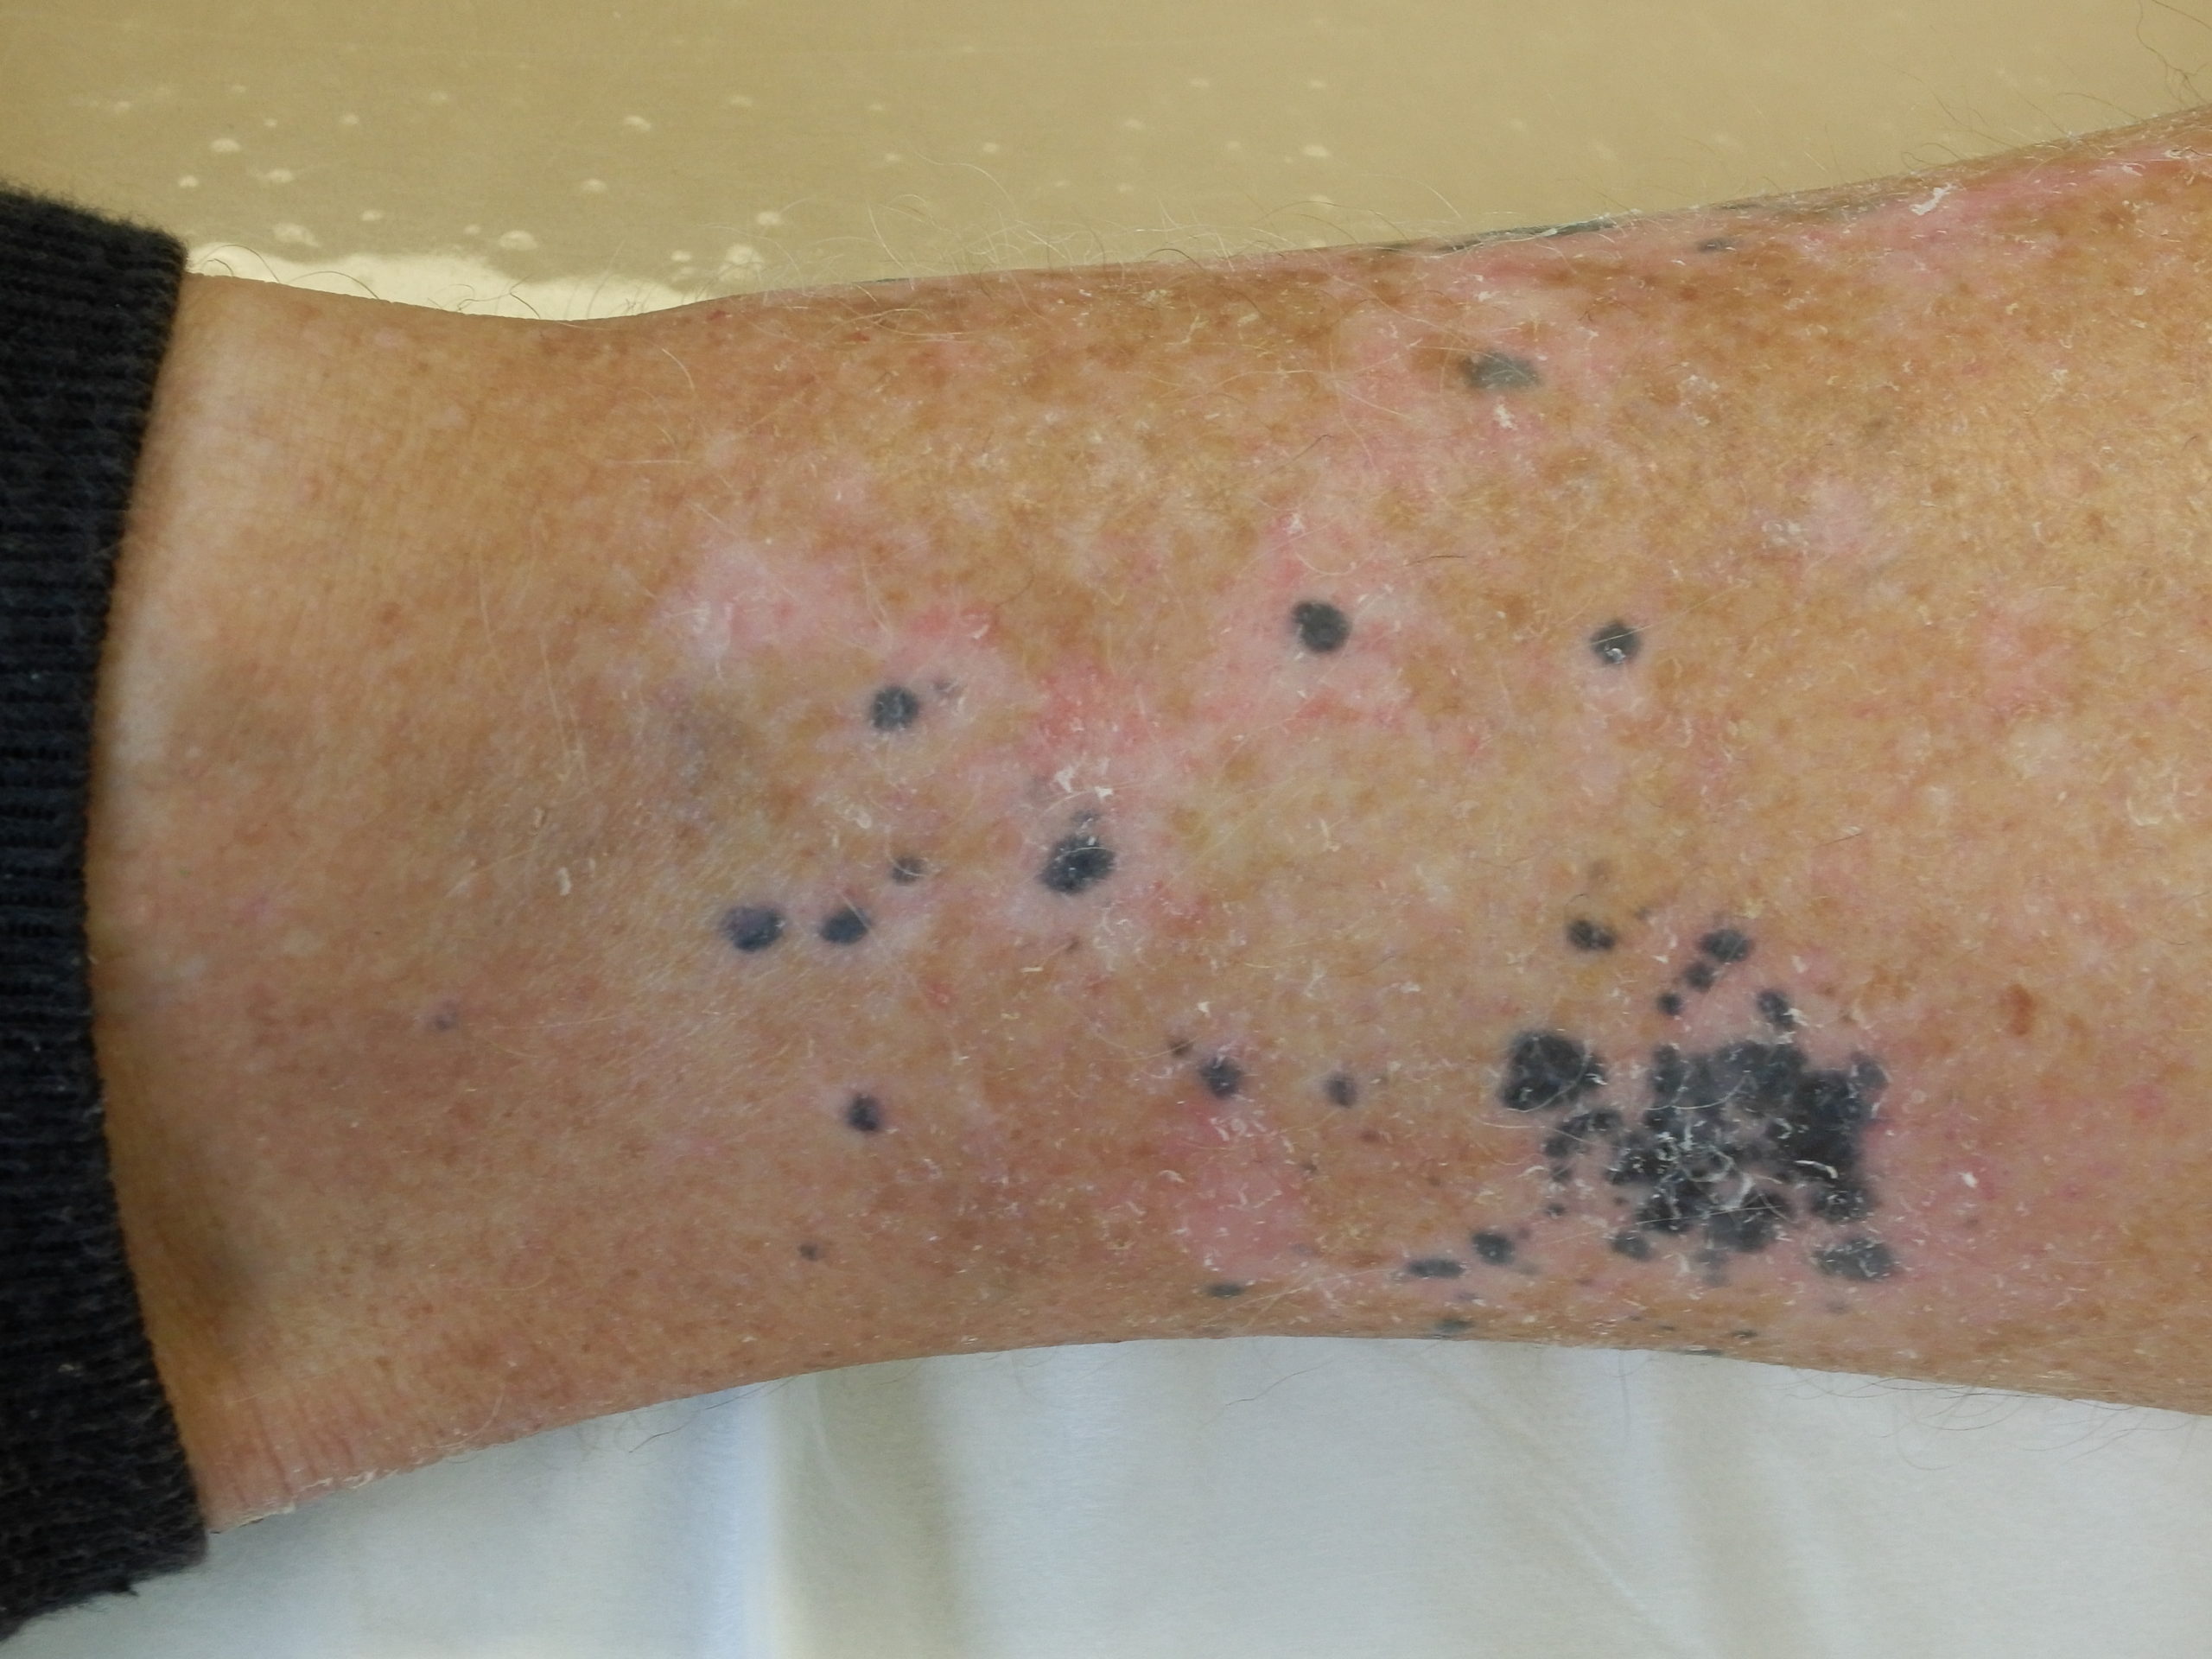

Site: Ankle

Diagnosis: Post Inflammatory Hyperpigmentation

Description: Note the perilesional hypopigmentation

These lesions arose after he went on Check Point inhibitor for metastatic melanoma. Note the perilesional hypopigmentation as well as the post inflammatory hyperpigmentation which was all that was left of his melanoma metastases. These had been stable for the last 9 months with no evidence in PET scans of melanoma elsewhere. This rteally shows the effectiveness of these immune stimulating drugs in metastatic melanoma.